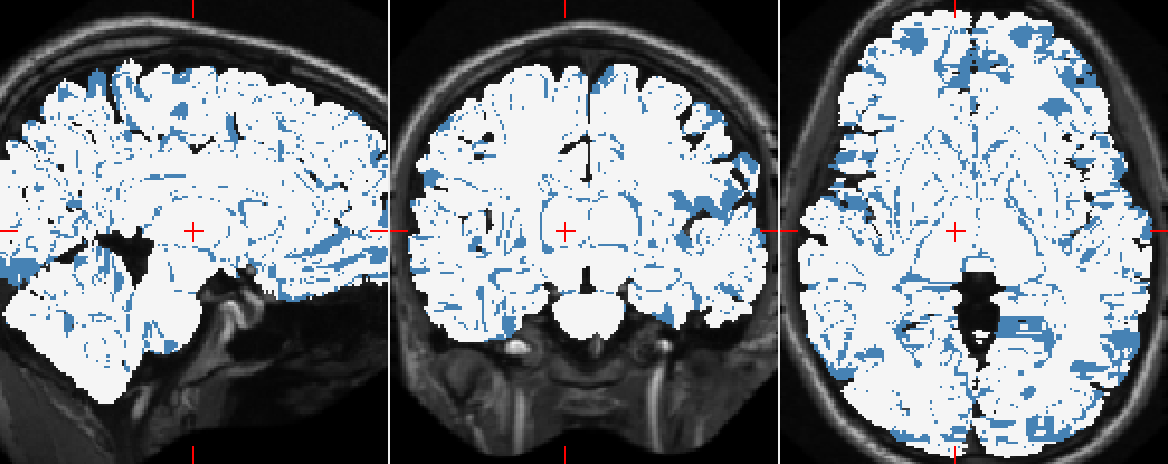

Figure 6 illustrates how well the downscaled patches and the distances to centroids enforce the global spatial consistency of the segmentations. Figure 7 shows the manual and automatic segmentations of a particular MRI. We notice that the misclassified voxels tend to lie on the boundaries of the regions, as expected.

Refer to caption

(a) Manual segmentation.

(b) Predicted segmentation.

(c) Difference, white voxels are identical while blue are different.

Figure 7: Comparison of the manual brain segmentation of a subject (ID: 1004) to that predicted by SegNet. The mean dice coefficient is 0.74.